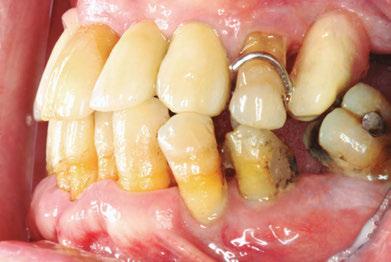

–Implantes híbridos en pacientes con antecedentes de periodontitis, por el Dr. Antonio Arnau y cols. [90]

–Implante inmediato en incisivo lateral superior con técnica de «Socket Shield» y acceso vestibular para legrado de la lesión periapical, por el Dr. Ignacio Tormo Jiménez y cols. [106]